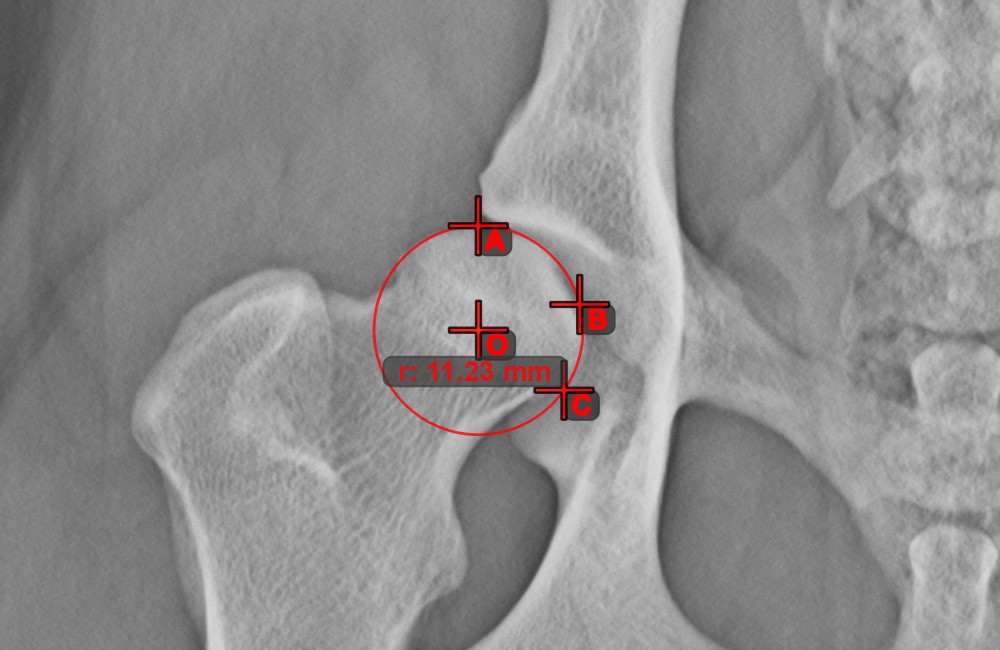

Circle from 3 Points¶

The Circle from 3 Points

tool is a simple and effective way to create a circle from just three points.

Start by selecting the tool from the left toolbar and assign it to one of the available mouse buttons. Place the three points of the circle, or select the points from ones available on the scene. The circle will be automatically created based on the position of the three points. The origo of the circle will always be marked with O. The radius of the circle is automatically calculated.

Modify the position of the three points to change the radius of the circle by using the Select/Move Item

tool.